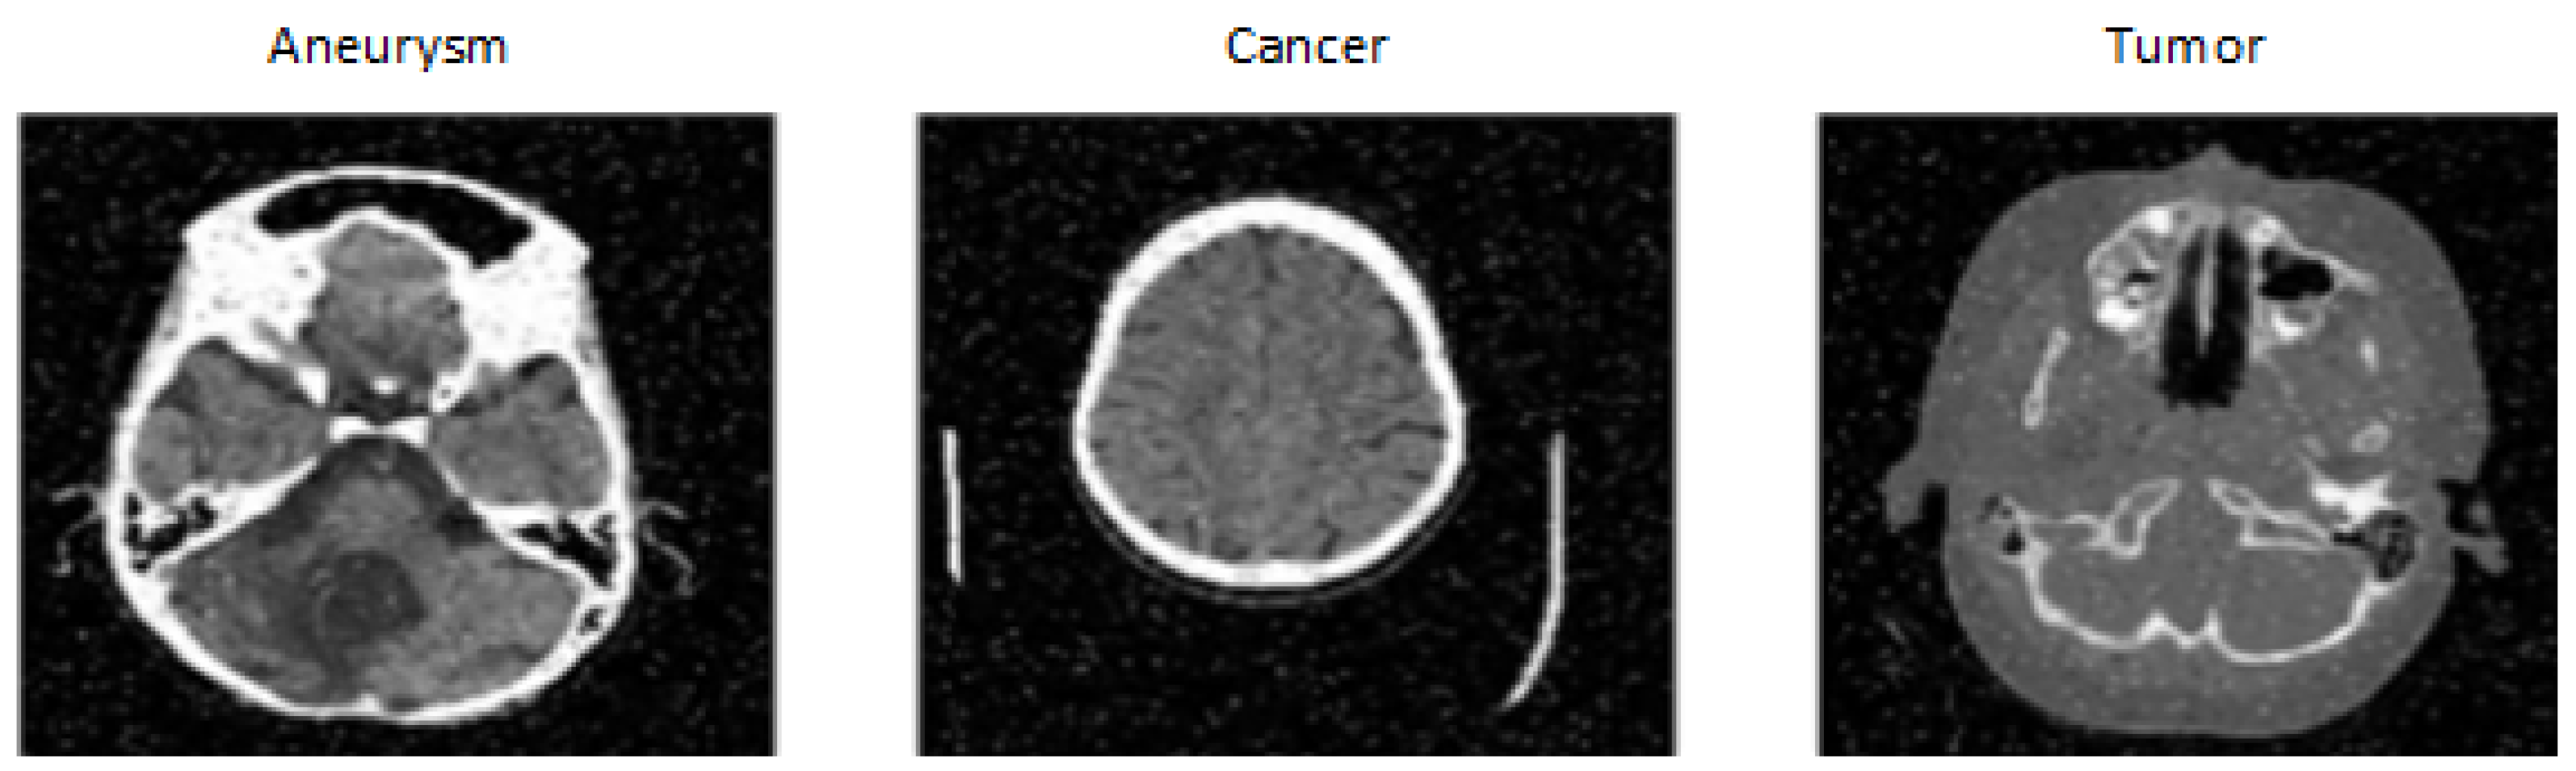

The dataset was created by DiscoverAI [17], for the general public to train neural networks and achieve results in the detection of aneurysms, tumors and cancer. This dataset contains 611 images from CT (see Figure 4) on which the given diseases occur. CT images are resized to 640 × 640. The images in the dataset also contain significant noise up to 5% of pixels. Images with noise can complicate disease classification. The dataset consists of three classes:

• Aneurysm: contains only CT images showing different types of intracranial aneurysms.

• Tumor: contains only CT images showing different types of tumors occurring in the brain.

• Cancer: contains only CT images showing different types of cancer in the brain.

Figure 4. Tumor, Cancer and Aneurysm Detection Image Dataset [17].

We chose this dataset because of the change in the modality of availability of CT images and the inclusion of several classes containing three different diseases. This makes classification more challenging, as a tumor in the area of a blood vessel can be mistaken for an aneurysm, and vice versa. The dataset is divided into training, testing and validation sets in the ratio 87:8:5. Another important factor in selecting this dataset was that the company Roboflow also published a model on this dataset, achieving a total validation accuracy of 98%, which we aimed to match while also speeding up the classification time [17].